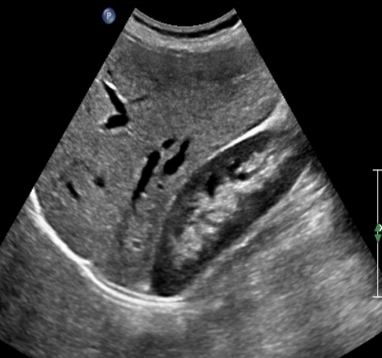

Identify this image.

Cirrhosis